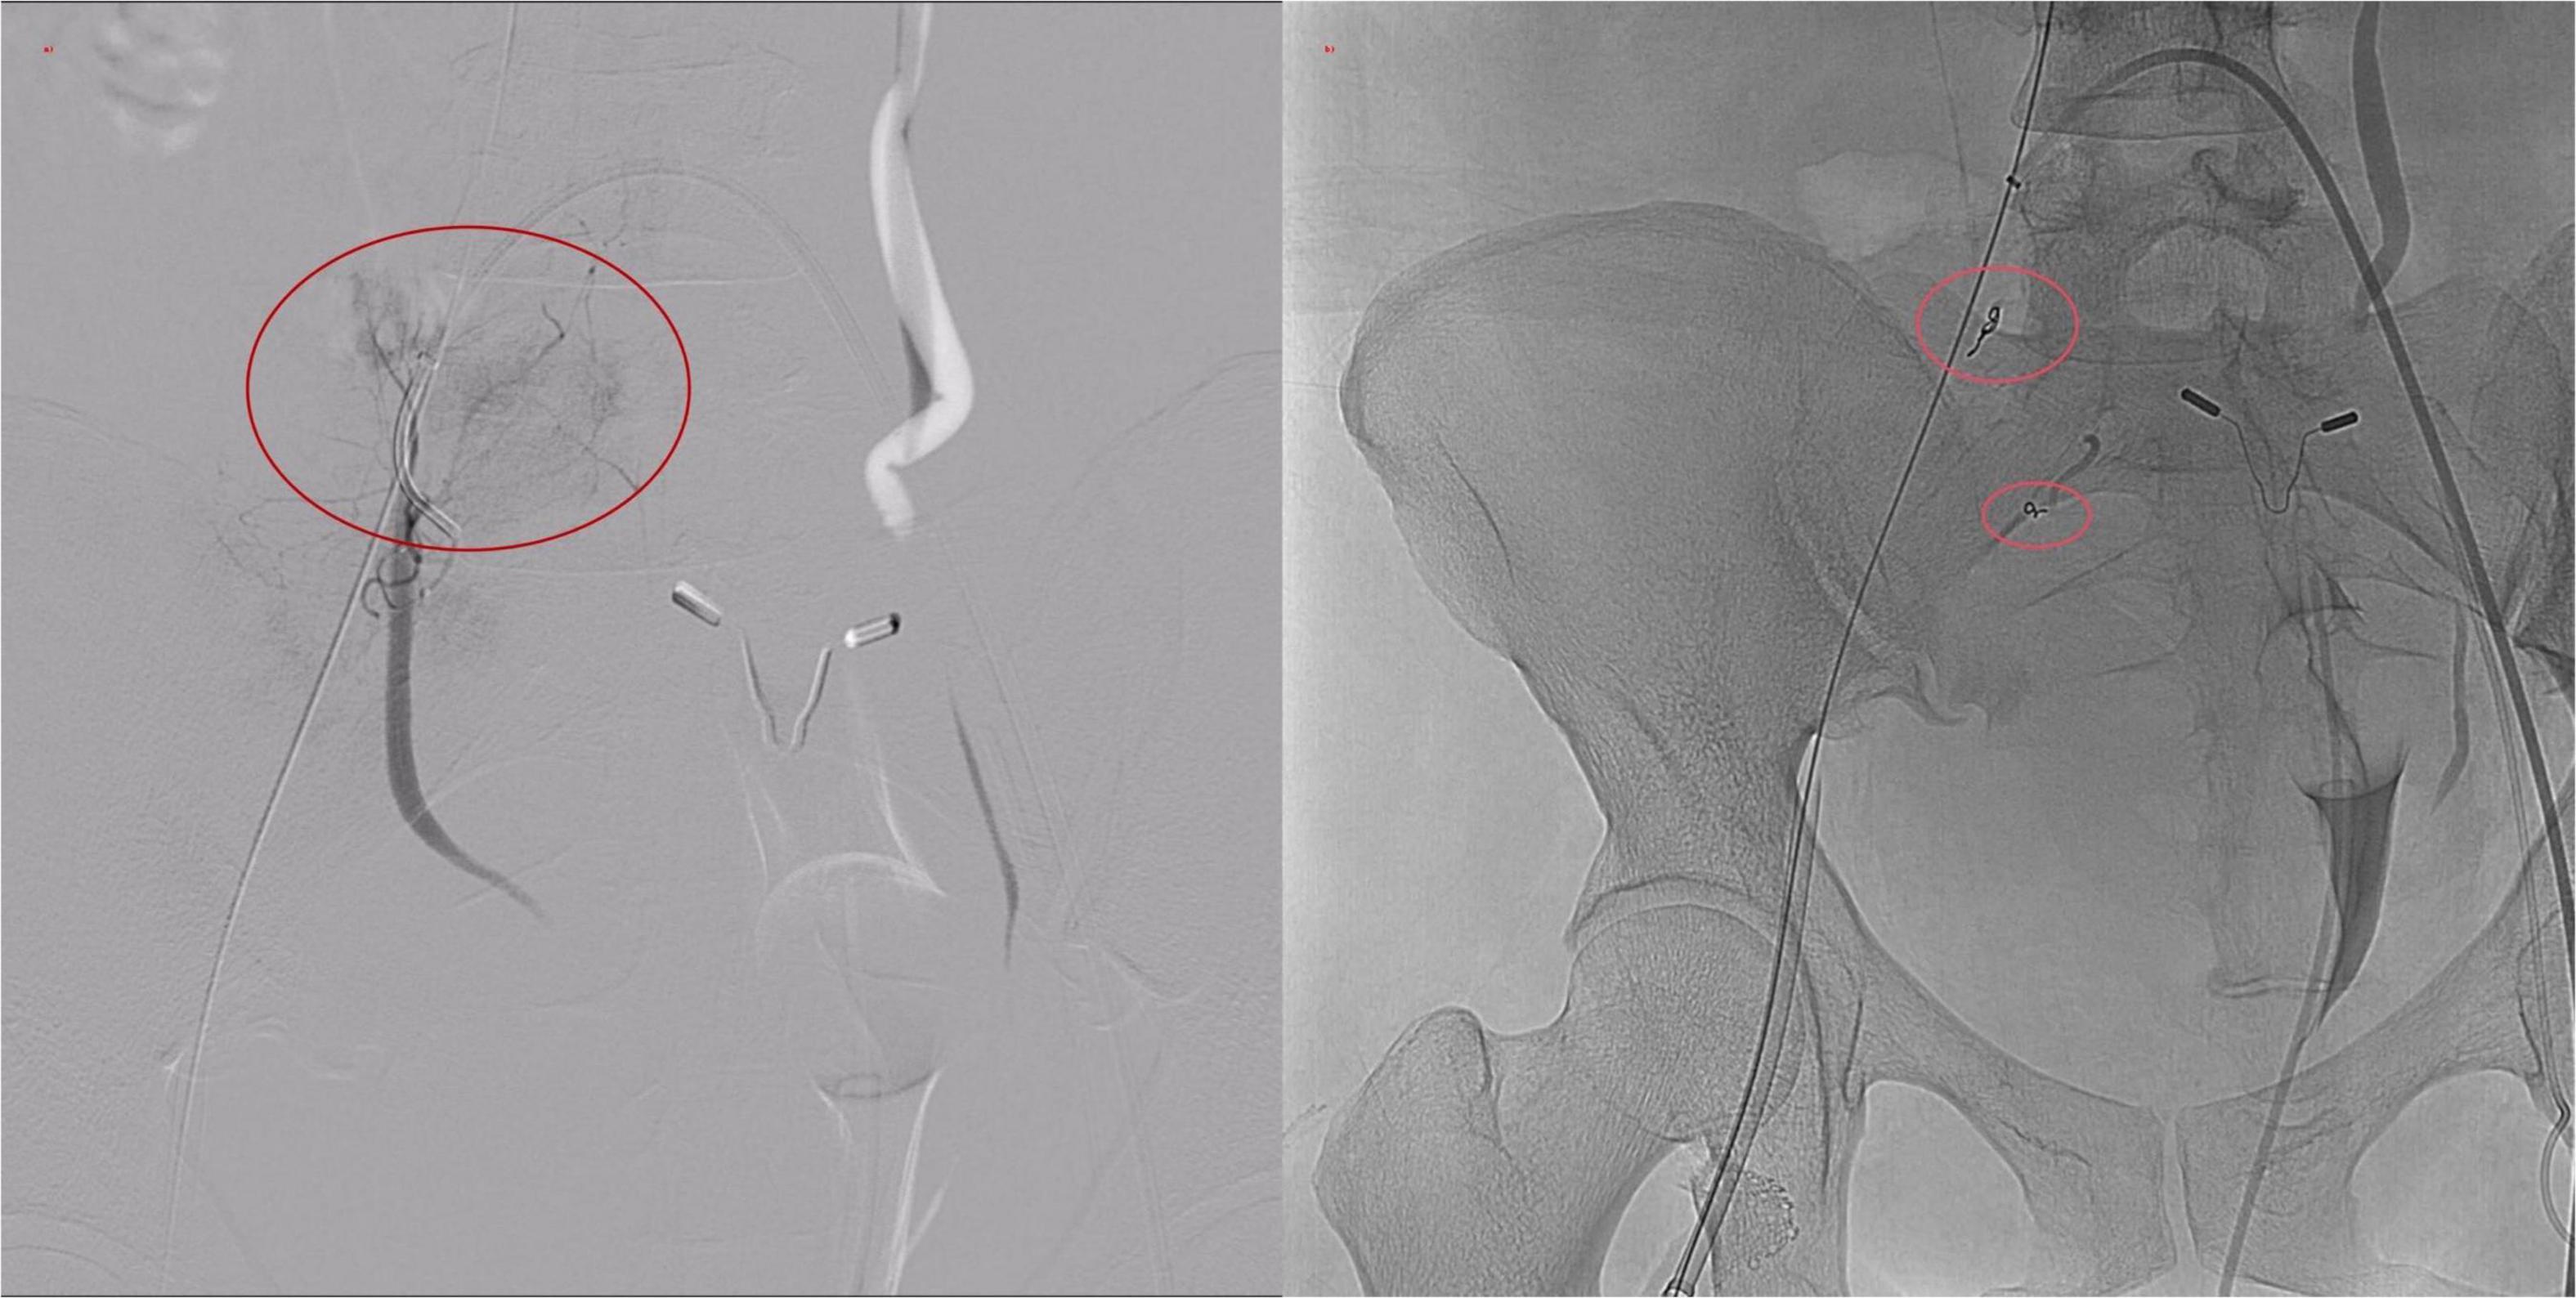

Resuscitation included fluid replacement, transfusion of leukocyte-depleted red cells and fresh frozen plasma, and norepinephrine infusion. Bedside ultrasound showed intra-abdominal fluid and a hypoechoic pelvic mass. Abdominal CT confirmed hemoperitoneum with loculated fluid collections up to 106 × 77 mm. Emergency digital subtraction angiography (DSA) was performed (Figure 3).

DSA revealed no extravasation along the venous access or iliac vein trajectory. The right femoral, common iliac, and external iliac arteries appeared intact. However, active contrast extravasation was identified in a branch of the right internal iliac artery. Endovascular embolization was performed, yielding immediate hemodynamic improvement (Figure 4). Post-procedure HGB levels stabilized between 72–77 g/L at 1, 4, and 10 h postoperatively, and the patient’s condition gradually improved.

Figure 4. Digital subtraction angiography (DSA) images. (a) Active contrast extravasation from a distal branch of the internal iliac artery. (b) Post-embolization angiogram demonstrating successful occlusion of the bleeding site with metallic coils.